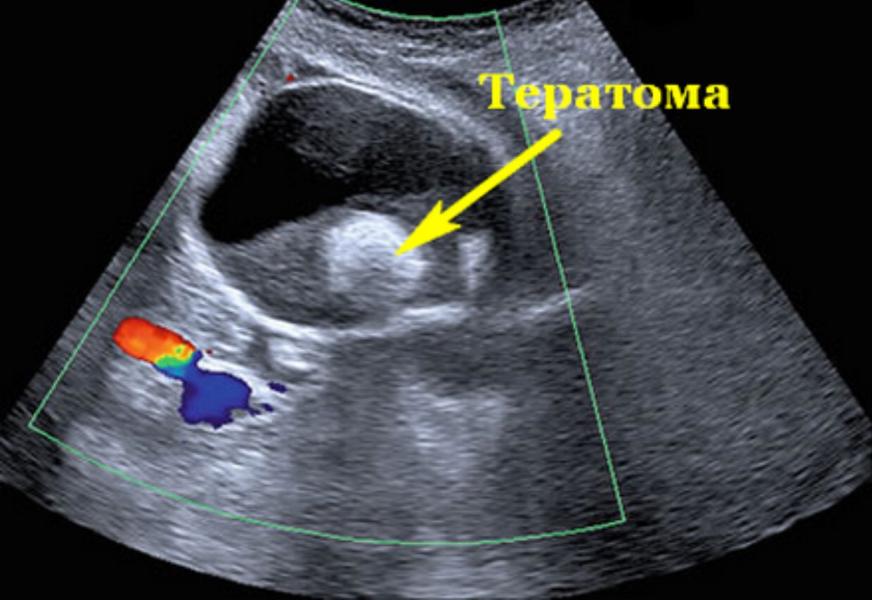

Сегодня на УЗИ поставили этот диагноз под вопросом, сказали ждать 3 месяца и снова на УЗИ.